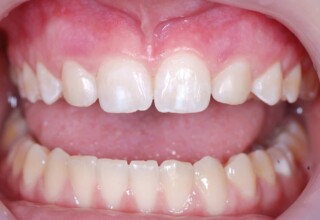

Όψεις Σύνθετης Ρητίνης

Οι όψεις ρητίνης προσφέρουν έναν οικονομικό τρόπο αισθητικής βελτίωσης της εμφάνισης των προσθίων δοντιών ενίοτε και των προγομφίων. Οι δυνατότητες τους πολλές, μπορούν να κάνουν και θαύματα! Ο μονός περιορισμός η κλινική ευχέρεια και η φαντασία του επεμβαίνοντος. Σε αυτήν την ασθενή οι τέσσερεις άνω τομείς είχαν ο καθένας το δικό του πρόβλημα(δυσχρωμία, απόκλιση) και επιπλέον: διαστήματα, πολλαπλές αποχρώσεις, κακή σχέση μεταξύ τους και με τα ούλα. Αποκαταστάθηκαν με τέσσερεις άμεσες όψεις ρητίνης (η μια πάνω σε στεφάνη πορσελάνης εμφυτεύματος!!!) οι οποίες κατασκευάστηκαν ενδοστοματικά!